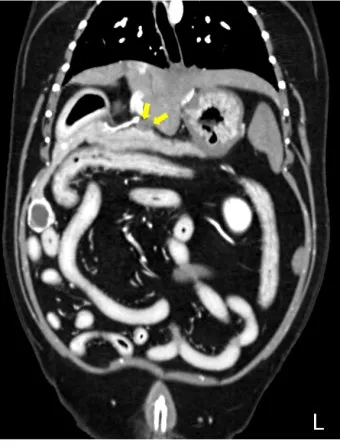

CT와 MRI 검사 - 초음파에서 의심스러운 소견이 발견되면 더 정밀한 검사를 진행해요. 특히 3D 영상으로 종양의 정확한 위치와 크기를 파악할 수 있어서 수술 계획을 세우는 데 필수적이에요.